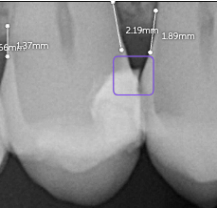

Bone Measurements

The system provides automated measurements from the crest of the bone to the cementoenamel junction (CEJ). These measurements are color-coded to indicate severity:

- White: 0-2.5 mm

- Yellow: 2.5-4 mm

- Amber: >4 mm

This feature is helpful for periodontal assessments, streamlining the process of identifying areas of bone loss. However, it's important to note that image angulation can affect the accuracy of these measurements, a limitation the system acknowledges.

I found these lines to be incredibly useful when describing patients' periodontal health. Cool feature, no doubt.